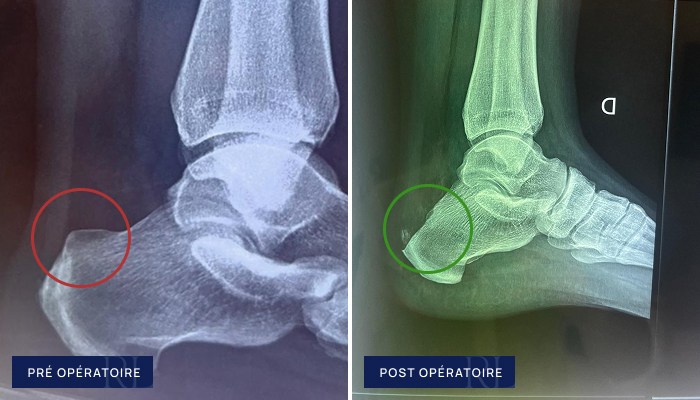

Radiographies pré et post opératoire de Tendinopathie d’Achille (Zadek)

À gauche : Tendinopathie chronique du tendon d’Achille (calcification dans le tendon d’Achille)

À droite : Correction mini invasive (ostéotomie de Zadek)